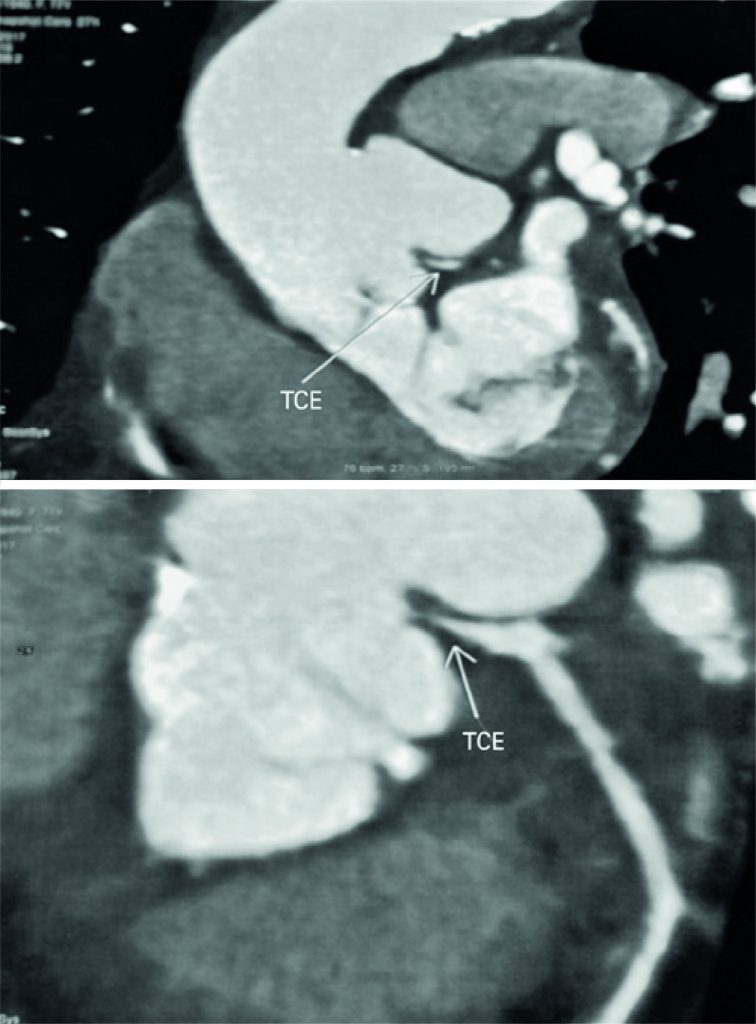

Figura 4

Angiotomografia demonstrando a compressão extrínseca do tronco da coronária esquerda. TCE: tronco de coronária esquerda.